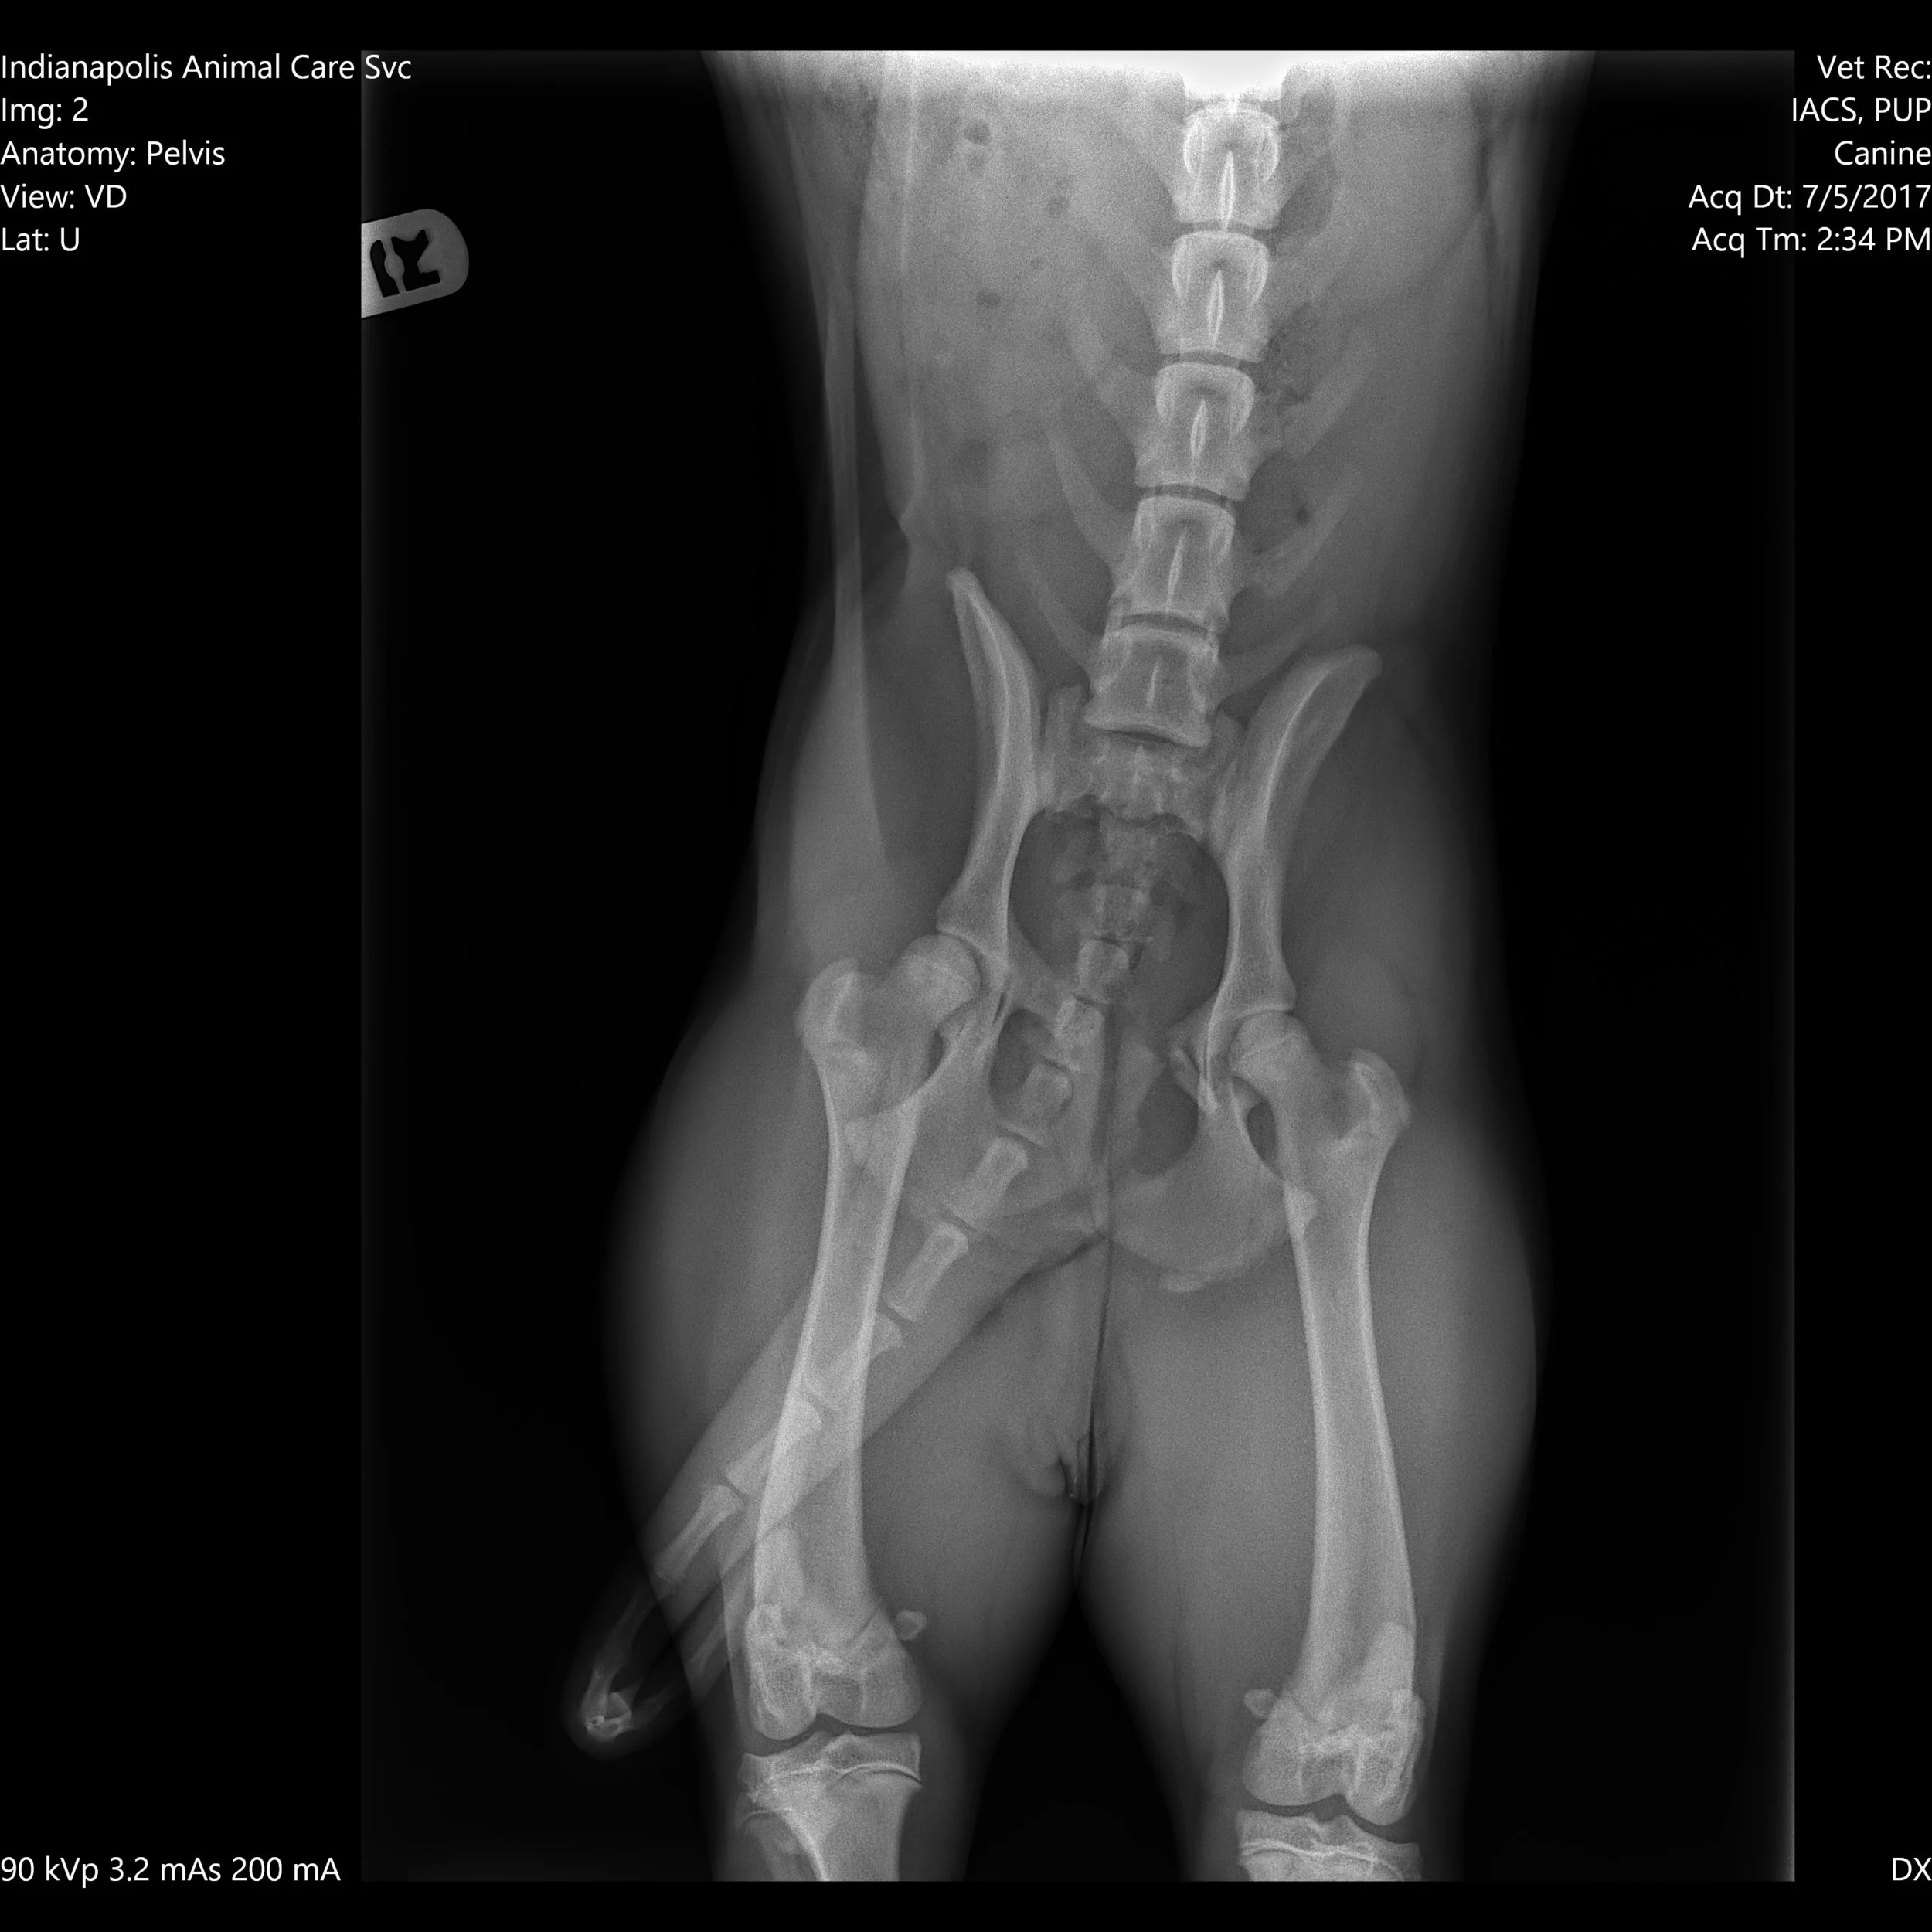

Hi I'm Millie. I'm recovering from a broken pelvis, but I'm still an affectionate gal. I just got the all-clear from my doctor to be scheduled for my spay surgery. My foster parents promise me the recovery won't be as bad as recovering from my current injury.